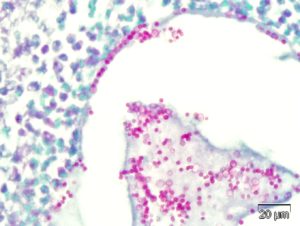

Murine models of pulmonary aspergillosis are important for the assessment of novel therapeutics and diagnostics, as well as for the study of disease pathogenesis. CBI has developed and validated a model of intratracheally-induced pulmonary aspergillosis infection in mice. In this model, an infection in the lung is established and then various modalities for treatment are assessed. Endpoints may include:

- Fungal culture

- Histopathology

- Clinical pathology